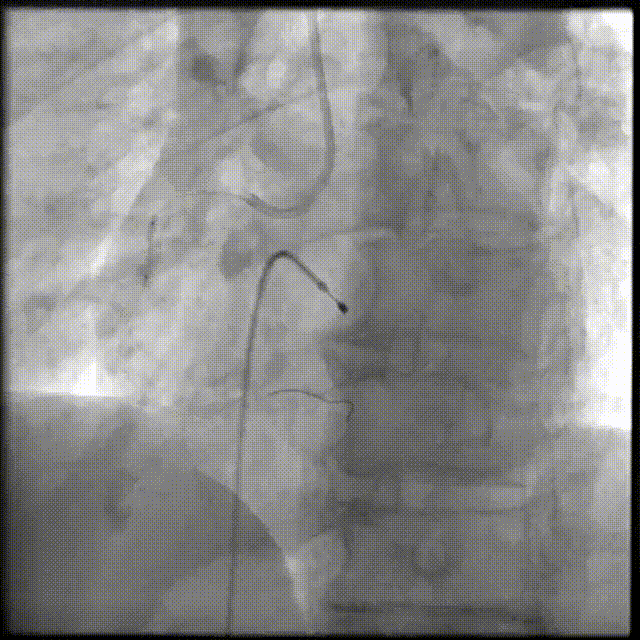

PCI过程-DES植入

由远及近依次送4.0X23mm、4.0X29mm、4.0X13mm DES至病变处串联释放。

PCI过程-支架后造影